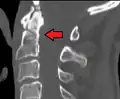

A fracture of both pedicles of the axis is termed a Hangman's fracture.

Fractures of the dens are classified into three categories according to the Anderson Alonso system:

- Type I fracture - Extends through the tip of the dens. This type is usually stable.

- Type II fracture - Extends through the base of the dens. It is the most commonly encountered fracture for this region of the axis. This type is unstable and has a high rate of non-union.

- Type III fracture - Extends through the vertebral body of the axis. This type can be stable or unstable and may require surgery.[1]

-

A fracture of the base of the dens as seen on plain X-ray -

A fracture of the base of the dens as seen on CT -

Type 3 odontoid fracture -

Type 2 dens fracture